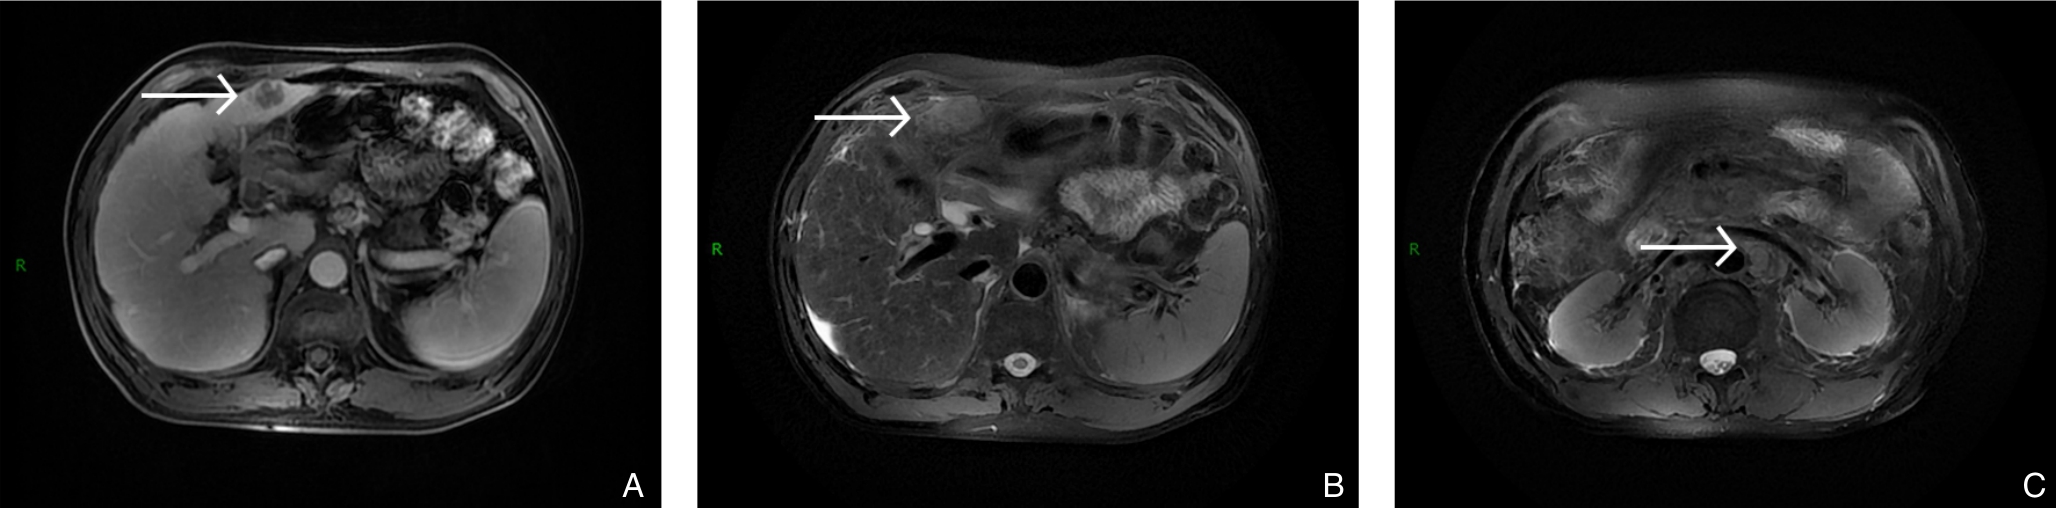

2025, 34(8):1783-1789. doi: 10.7659/j.issn.1005-6947.250076

摘要:背景与目的 肝内胆管癌(ICC)是一种起病隐匿、预后极差、初诊多为进展期的原发性肝癌,其治疗选择有限,预后差。本研究旨在探讨靶向治疗、免疫治疗与肝动脉灌注化疗(HAIC)联合应用于晚期ICC的转化治疗的潜力,为临床转化治疗提供参考。方法 回顾广东医科大学附属医院2021年11月收治的1例晚期ICC行靶向治疗、免疫治疗与HAIC联合治疗后成功转化并接受手术患者的诊治过程,并复习国内外相关文献。结果 患者为52岁男性,确诊为T2N1M0-Ⅲb期ICC。患者拒绝接受以吉西他滨联合顺铂为主的一线化疗方案,同意行靶向治疗联合免疫治疗与HAIC的综合治疗,在接受4个治疗周期后评估肿瘤达到部分缓解,具备实施根治性手术治疗的条件。患者随后接受了腹腔镜下肝S6段和部分S7段切除、胆囊切除以及肝门部和腹膜后淋巴结清扫术。术后患者规律行靶向免疫联合化疗的综合治疗方案。在疾病出现复发和转移后,化疗药物进行了相应调整。截至目前,患者无病生存期达15个月,总生存期超过3年。结论 靶向治疗、免疫治疗与HAIC三联方案可提高晚期ICC患者的转化机会并延长生存期,具有较好的安全性和临床应用前景,但其疗效仍需多中心研究进一步验证。